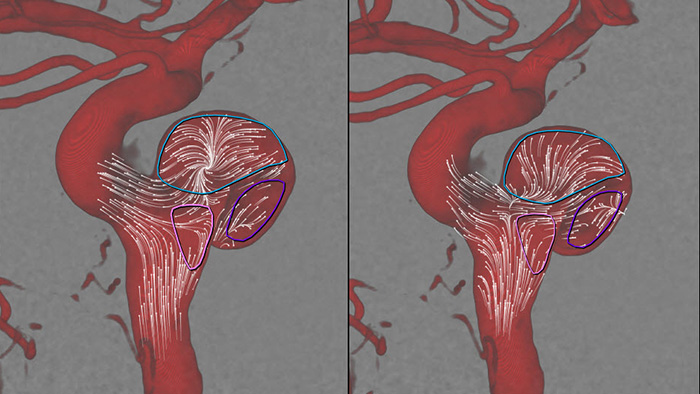

Mejorar la evaluación de riesgos

MR-CT Roadmap

MR-CT Roadmap ofrece la posibilidad de superponer una exploración previamente adquirida de SmartCT Angio o MR angio con la fluoroscopia en vivo para visualizar los límites de la lesión y la vascularización correspondiente para evaluar riesgos. La reutilización de información preadquirida le ayuda a administrar la dosis de los rayos X y del medio de contraste.